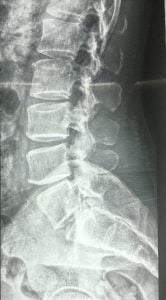

Figure showing Xray & MRI plate. A digital xray gives a proper image of the spine , while the MRI gives a detailed picture of the Spine with nerves and the spinal cord visualised clearly

- Apart from an MRI other Radiological investigations like an Xray is also required. Its best to get a Digital Xray done, The quality and resolution is the best and this is important for the surgeon. The planning for a surgery also depends on a good quality X ray.